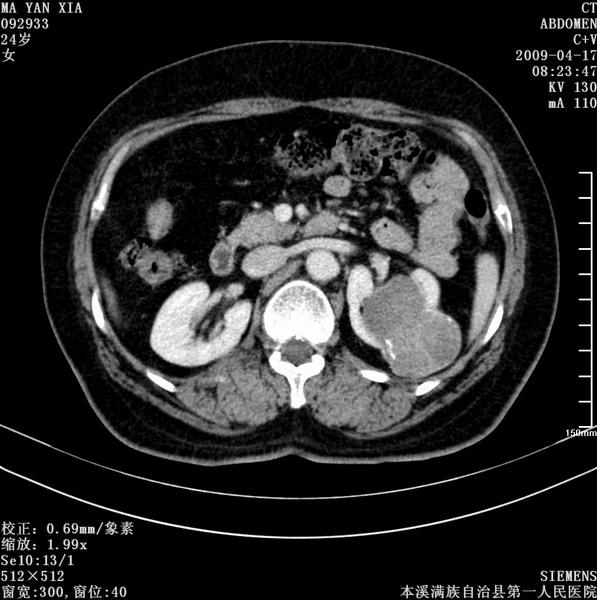

标题: CT19443:肾脏肿瘤两个区强化不一样。 [打印本页]

标题: CT19443:肾脏肿瘤两个区强化不一样。

女,51岁,体检时发现肾脏占位,建议ct增强。无任何自觉症状。

典型的不均匀强化,左肾癌